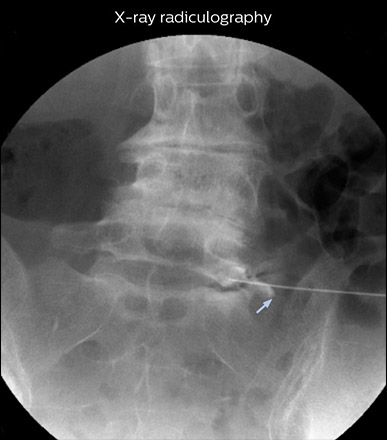

“In such case, we would then browse through axial T2-weighted MR images slice by slice and mentally reconstruct the actual situation based on both radiculography and MRI. Fortunately, NerveVIEW can now very well show nerve courses and presence of nerve compression or edema in one single image series.” “We have often seen NerveVIEW directly depict details of the nerve compression that were not observed by radiculography. Therefore, we think that with NerveVIEW we can reduce the number of invasive examinations, especially for some patients with lumbar plexus symptoms.”

“Before NerveVIEW, diagnosis by MRI alone was sometimes difficult, unless there was a strong suspicion based on clinical symptoms,” says Shoji Yabuki, MD, DMSc, Orthopedic surgeon at Fukushima Medical University School of Medicine. “This is why we routinely perform selective lumbosacral radiculography (nerve root block) and x-ray in such cases. However, radiculography can only depict nerves as far as the contrast agent reaches. When a nerve is distorted by compression, the contrast agent will not pass through this compressed area, preventing us from evaluating the full nerve compression.”

The key concept in MR neurography, Dr. Yabuki stresses, is the ability to directly visualize spinal nerves, versus inferring the presence of pathology indirectly. “Before NerveVIEW, we estimated compression of the nerve by looking for the presence or absence of fat signal on other MR images,” he says.